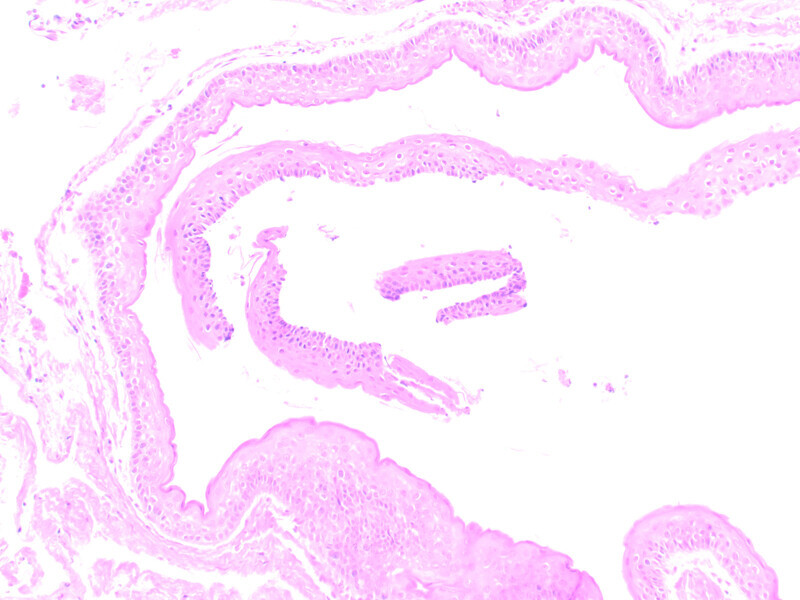

Śródkostna postać torbieli naskórkowej zlokalizowana w żuchwie – opis przypadku